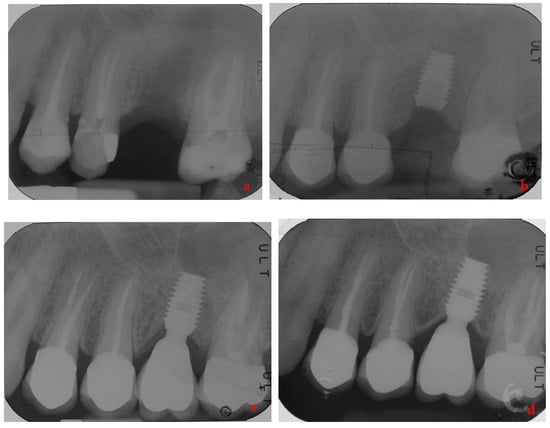

- Lombardo, G.; Signoriello, A.; Simancas-Pallares, M.; Marincola, M.; Nocini, P.F. Survival of Short and Ultra-Short Locking-Taper Implants Supporting Single Crowns in the Posterior Mandible: A 3-Year Retrospective Study. J. Oral Implant. 2020, 46, 396–406. [Google Scholar] [CrossRef] [PubMed]

- Lombardo, G.; Marincola, M.; Signoriello, A.; Corrocher, G.; Nocini, P.F. Single-Crown, Short and Ultra-Short Implants, in Association with Simultaneous Internal Sinus Lift in the Atrophic Posterior Maxilla: A Three-Year Retrospective Study. Materials 2020, 13, 2208. [Google Scholar] [CrossRef] [PubMed]